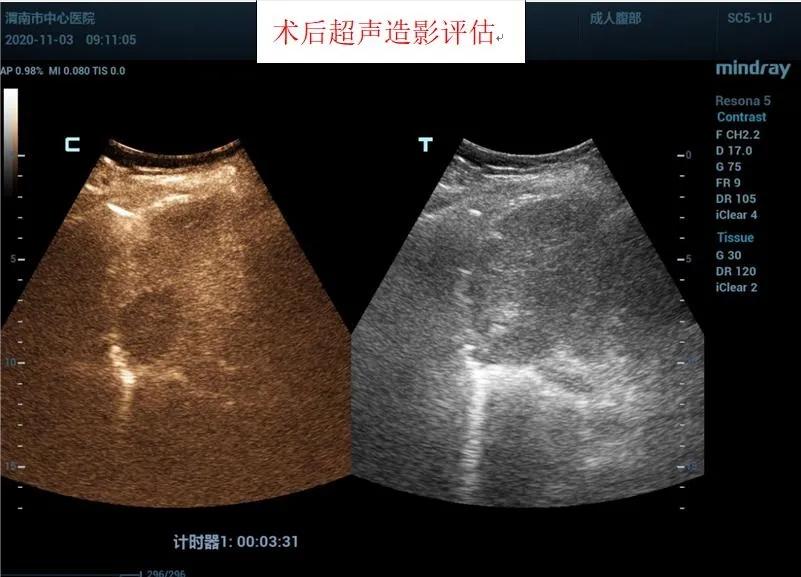

在王建宏教授的指导下,华玺副主任医师、韩婷婷主治医师的默契配合下,经过20余分钟,手术顺利完成,术后安返病房。术后3天超声造影进行评估,显示消融处呈无增强,提示达到预期治疗效果且患者精神状态良好。

据超声科刘晓晖主任介绍,超声造影技术联合微波消融术可以在术前更明确的反映肿瘤病灶的实际大小及其浸润范围,可将微波治疗范围以超声造影测值作为参考,从而更客观的判断肿瘤病灶大小及周围浸润情况,确认需治疗的范围,同时可以使用超声造影在微波消融术中进行检测引导,术后通过超声造影确认肿瘤是否完全灭活。该方法与传统外科手术相比创伤小,手术时间短,术中痛苦小,并发症极少;术后恢复快,缩短了住院时间,江南在线体育超声科将超声造影技术与微波消融术联合使用,为患者带来了新的治疗希望。